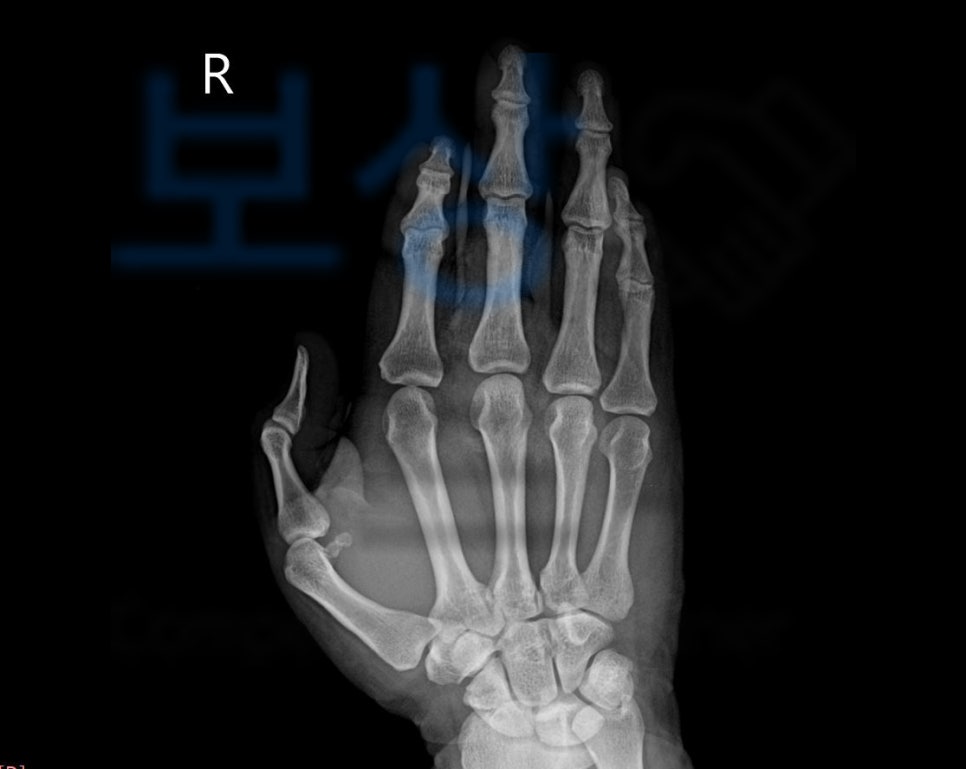

제 3,4,5수지 천수지굴건 및 심수지굴건 파열

힘줄 파열로 수술을 받았지만 위와 같이 손가락이 굽어 펴지지 않게 되었죠. 이와 같은 모습은

말렛핑거 (mallet finger)

즉 마치 손가락의 모양이 망치처럼 굽혀진 모양을 가리킵니다. 당신의 보험증권에서 “후유장해” 항목 찾아보세요. 보험증권을 보시면